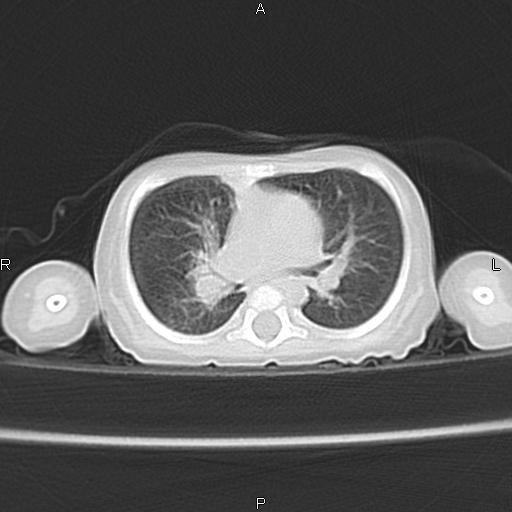

以下是引用jsdtd在2010-7-26 14:42:00的发言:[br]胸腺呈帆状,体位所致,没事。

以下是引用aa13877358820在2010-7-26 12:35:00的发言:[br]男性,三个月,卧位胸片,咳嗽、气促、发热14天,两肺闻及细小水泡音。[br]